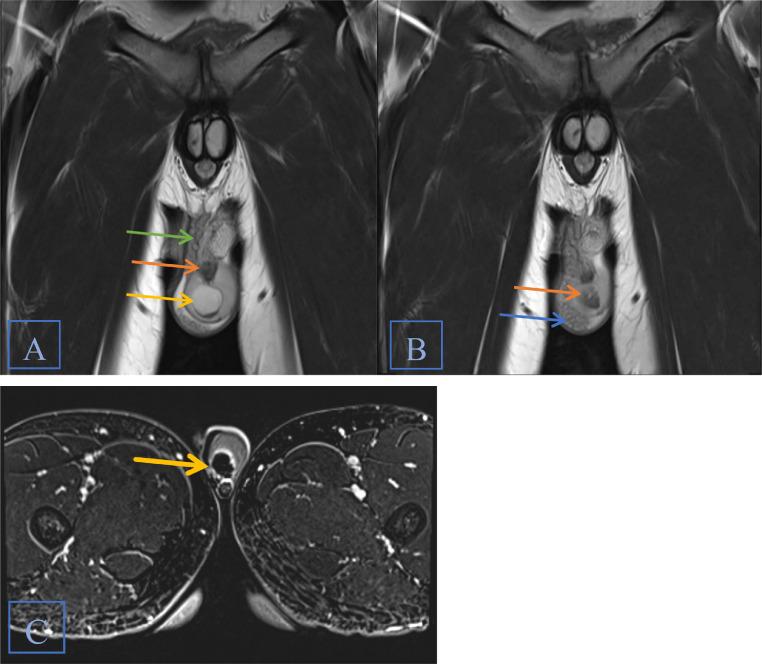

Zinner syndrome comprises a triad of unilateral renal agenesis, ipsilateral seminal vesicle cyst, and ejaculatory duct obstruction, which can be accompanied by additional abnormalities of the genitourinary tract in some cases. Patients may be asymptomatic or present with urinary, reproductive, and/or local pain symptoms. Diagnosis is most commonly achieved via MRI. Here, we present the case of an 18-year-old male previously diagnosed with unilateral renal agenesis, who presented with testicular and penile pain, along with urinary urgency and frequency. MRI of the abdomen and pelvis revealed all three components of Zinner syndrome as well as an ectopic ureter emptying into the seminal vesicle. Our case adds to the existing limited literature on this rare syndrome and broadens the understanding of how this syndrome can present both clinically and radiologically.

齐纳综合征包括单侧肾缺如、同侧精囊囊肿和射精管梗阻三联征,某些情况下可伴有泌尿生殖道的其他异常。患者可能无症状,或出现泌尿系统、生殖系统和/或局部疼痛症状。诊断最常用的方法是磁共振成像(MRI)。在此,我们报告一例18岁男性病例,该患者此前被诊断为单侧肾缺如,现出现睾丸和阴茎疼痛,伴有尿急和尿频。腹部和盆腔的MRI显示了齐纳综合征的所有三个组成部分,以及一条异位输尿管排入精囊。我们的病例补充了关于这种罕见综合征的现有有限文献,并拓宽了对该综合征在临床和影像学上表现的认识。